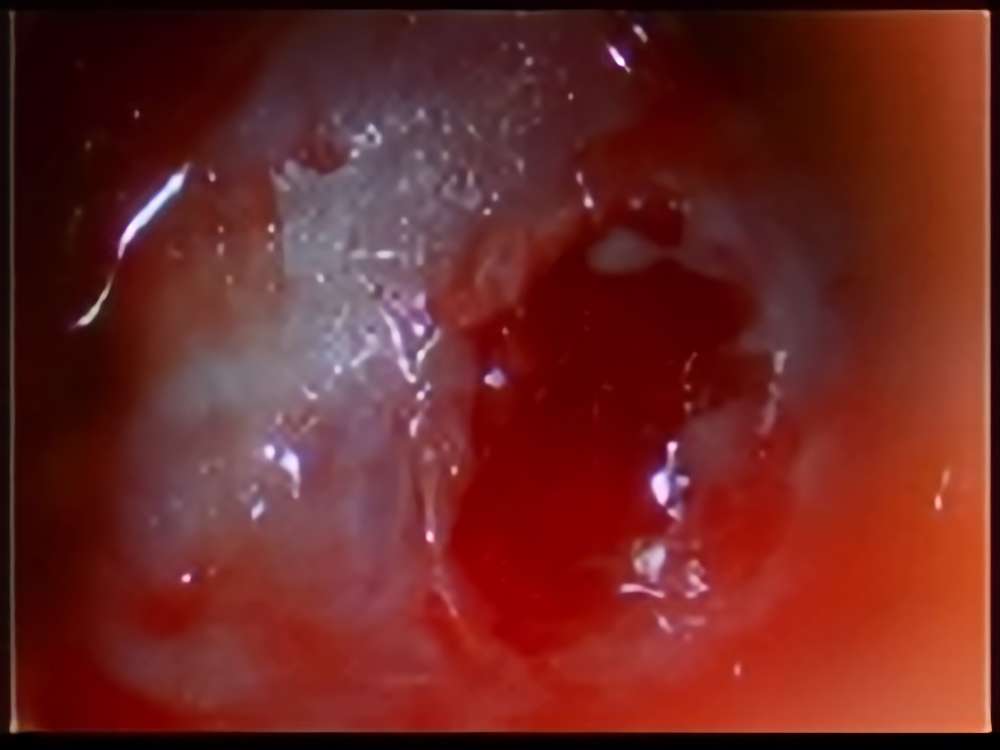

術中写真

摘出 後